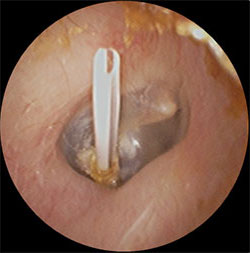

・上記の滲出性中耳炎の鼓膜に小さな切開をいれ、内部の液体を吸引し、鼓膜チューブを挿入

・左図の処置後から1週間後、鼓膜内側には液体は溜まっておらず、正常の鼓膜の色である